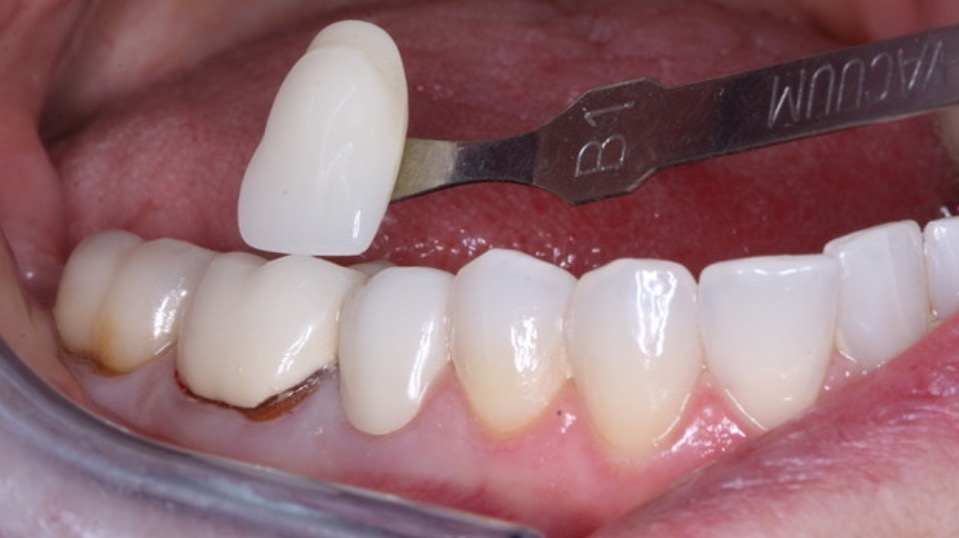

It is well proven microscopically that composite margins are open. Composite is not cariostatic. The concepts in this article can reduce or eliminate new caries around and under composite restorations. When you add that information to the use of resin-modified or conventional glass ionomer used as a liner or dentin substitute, you can expect a significant reduction in new caries (figure 6).